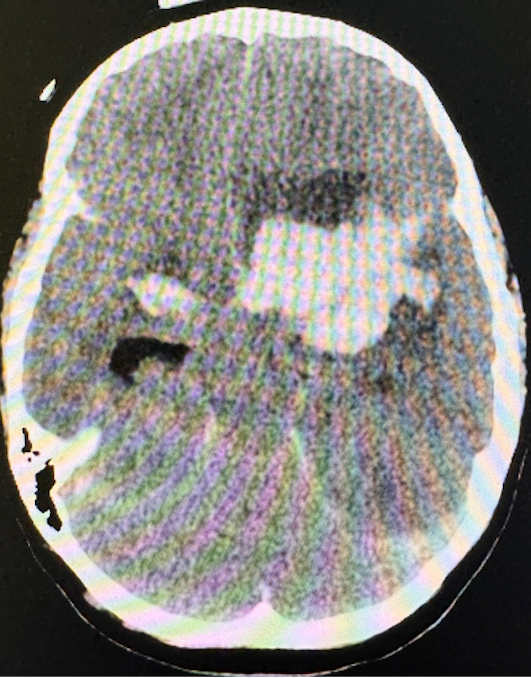

Durante i primi giorni di ricovero lo stato neurologico è fluttuante, ma con condizioni globali in lieve costante miglioramento. A circa 7 giorni dall’esordio la prognosi del nostro paziente si aggrava per un peggioramento dello stato neurologico, crisi ipertensiva (190/120 mmHg) e successiva anisocoria; effettua pertanto una TC che mostrerà un’infausta complicanza: un’emorragia cerebrale intraparenchimale massiva, in sede fronto-temporale sinistra (Figura 2).

L’encefalite erpetica non implica immunodeficit: anche soggetti immunocompetenti possono esserne affetti. Tuttavia, data la rarità della condizione, tutti i pazienti in benessere andrebbero studiati con tipizzazione linfocitaria e signature interferonica (possibili deficit di TLR3)2. L’EEG può aiutarci nelle prime fasi di sospetto clinico essendo alterato già precocemente in più dell’80% dei casi. Al neuroimaging la presentazione tipica è quella di un’encefalite necrotizzante: gli spot microemorragici sono di riscontro frequente ma il sanguinamento massivo è un’evenienza rarissima3 (circa 30 casi descritti in letteratura). Ricordiamo che il neuroimaging va ripetuto in caso di peggioramento neurologico anche in corso di terapia e che alcuni pazienti potrebbero necessitare di neurochirurgia.